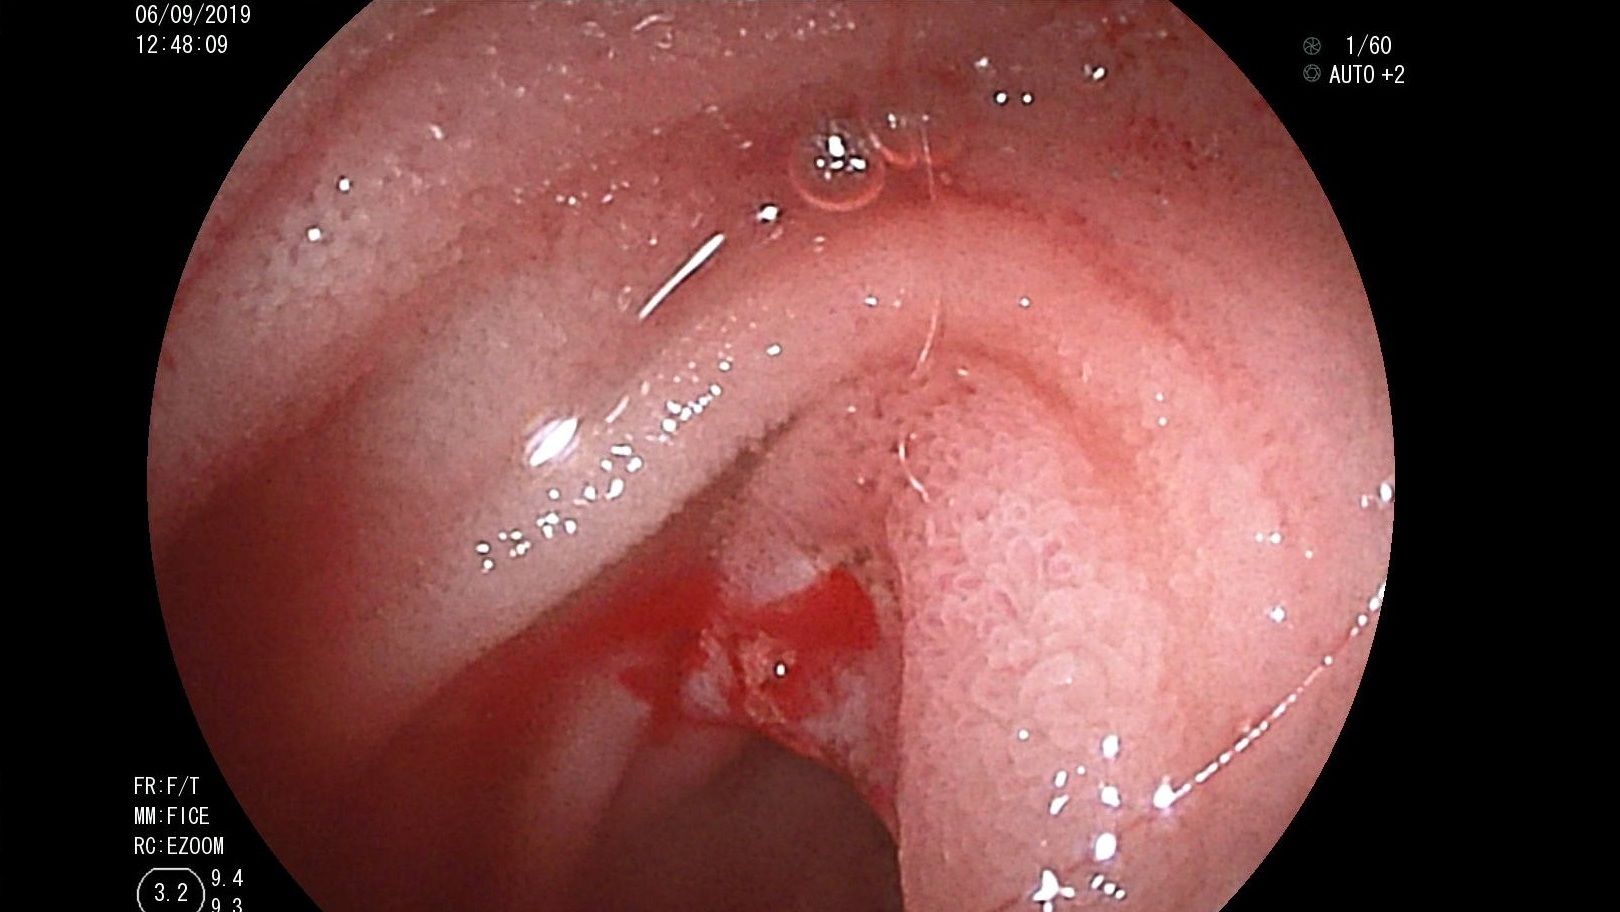

Bệnh viện Trường Đại học Y Dược Huế triển khai thành công phẫu thuật đặt thể hang nhân tạo cho bệnh nhân rối loạn cương nặng

Rối loạn cương là một bệnh lý tuy không nguy hiểm tính mạng nhưng ảnh hưởng rất nhiều đến chất lượng cuộc sống, không chỉ riêng bệnh nhân mà còn với...